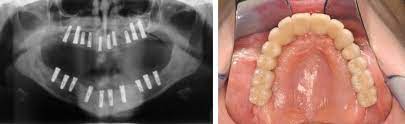

Implantologie Mkg Chirurgie Praxis Im Spitaler Hof Hamburg

Implantologie Mkg Chirurgie Praxis Im Spitaler Hof Hamburg from www.mkg-hamburg-zentrum.de